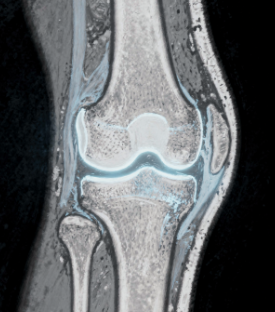

8. 반월상 연골 손상

무릎 안에 있는 반월상 연골이 손상되면 움직일 때 소리가 날 수 있습니다.

특히 무릎이 걸리는 느낌이나 통증이 함께 나타날 수 있습니다.